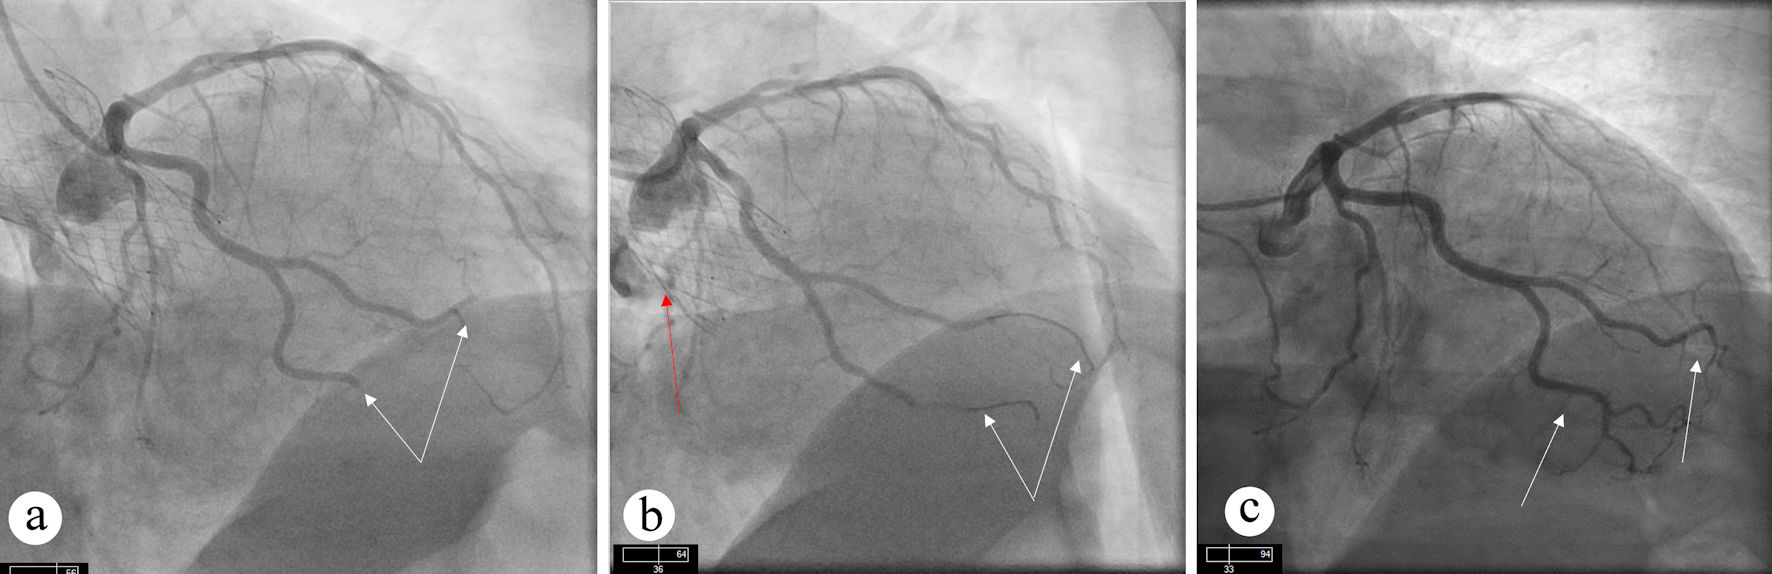

Twenty-nine months later, he presented with inferolateral STEMI. Coronary angiography showed complete occlusion of an OM branch (Fig. 3a). Despite multiple attempts with balloon angioplasty and aspiration thrombectomy, adequate coronary flow could not be restored (Fig. 3b). Notably, the pre-TAVR coronary angiogram demonstrated patent OM branches without any evidence of obstructive CAD (Fig. 3c).

Figure 3. Angiographic views showing persistent occlusion of OM branch. (a) Occlusion of OM artery (white arrow) can be seen. (b) Persistent occlusion of OM artery (white arrow) despite aspiration thrombectomy. TAVR valve (red arrow) can also be seen. (c) Diagnostic angiogram before TAVR procedure showing patent OM artery without obstructive CAD. CAD: coronary artery disease; OM: obtuse marginal; TAVR: transcatheter aortic valve replacement.